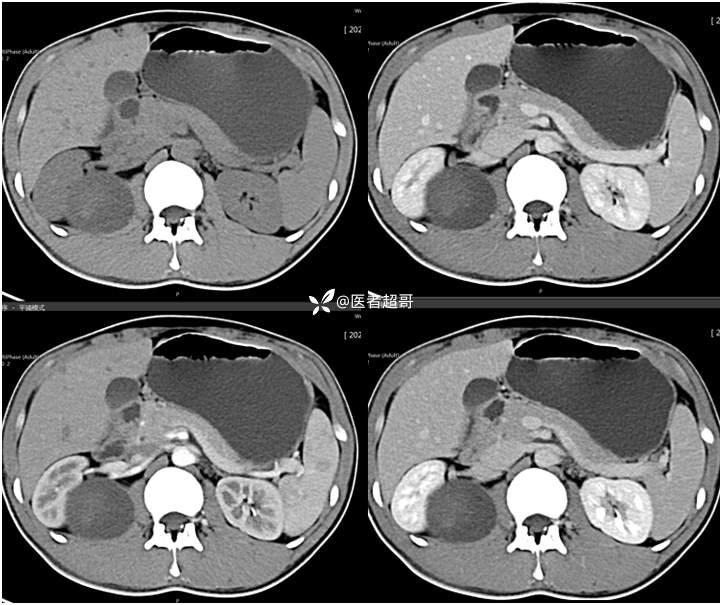

【影诊笔记754】腰痛就诊,腹膜后实性占位,请诊断分析!

主 诉:腰痛2月。

现病史:患者2月前无明显诱因出现腰背部疼痛,夜间为著。患者无头痛、头晕,无恶心、呕吐,无胸闷、憋气,无腹痛、腹胀。无尿频、尿急、尿痛等现象。患者在院外未作特殊治疗。为求进一步诊疗,来我院肾内科门诊就诊。门诊行双肾、输尿管、膀胱(前列腺)彩超提示:腹膜后实性占位。患者遂来我科就诊。我科以“腰痛”收治入院,患者自发病以来,神志清,精神可,饮食可,睡眠差。小便如上述,大便未见明显异常。体重无明显增减。